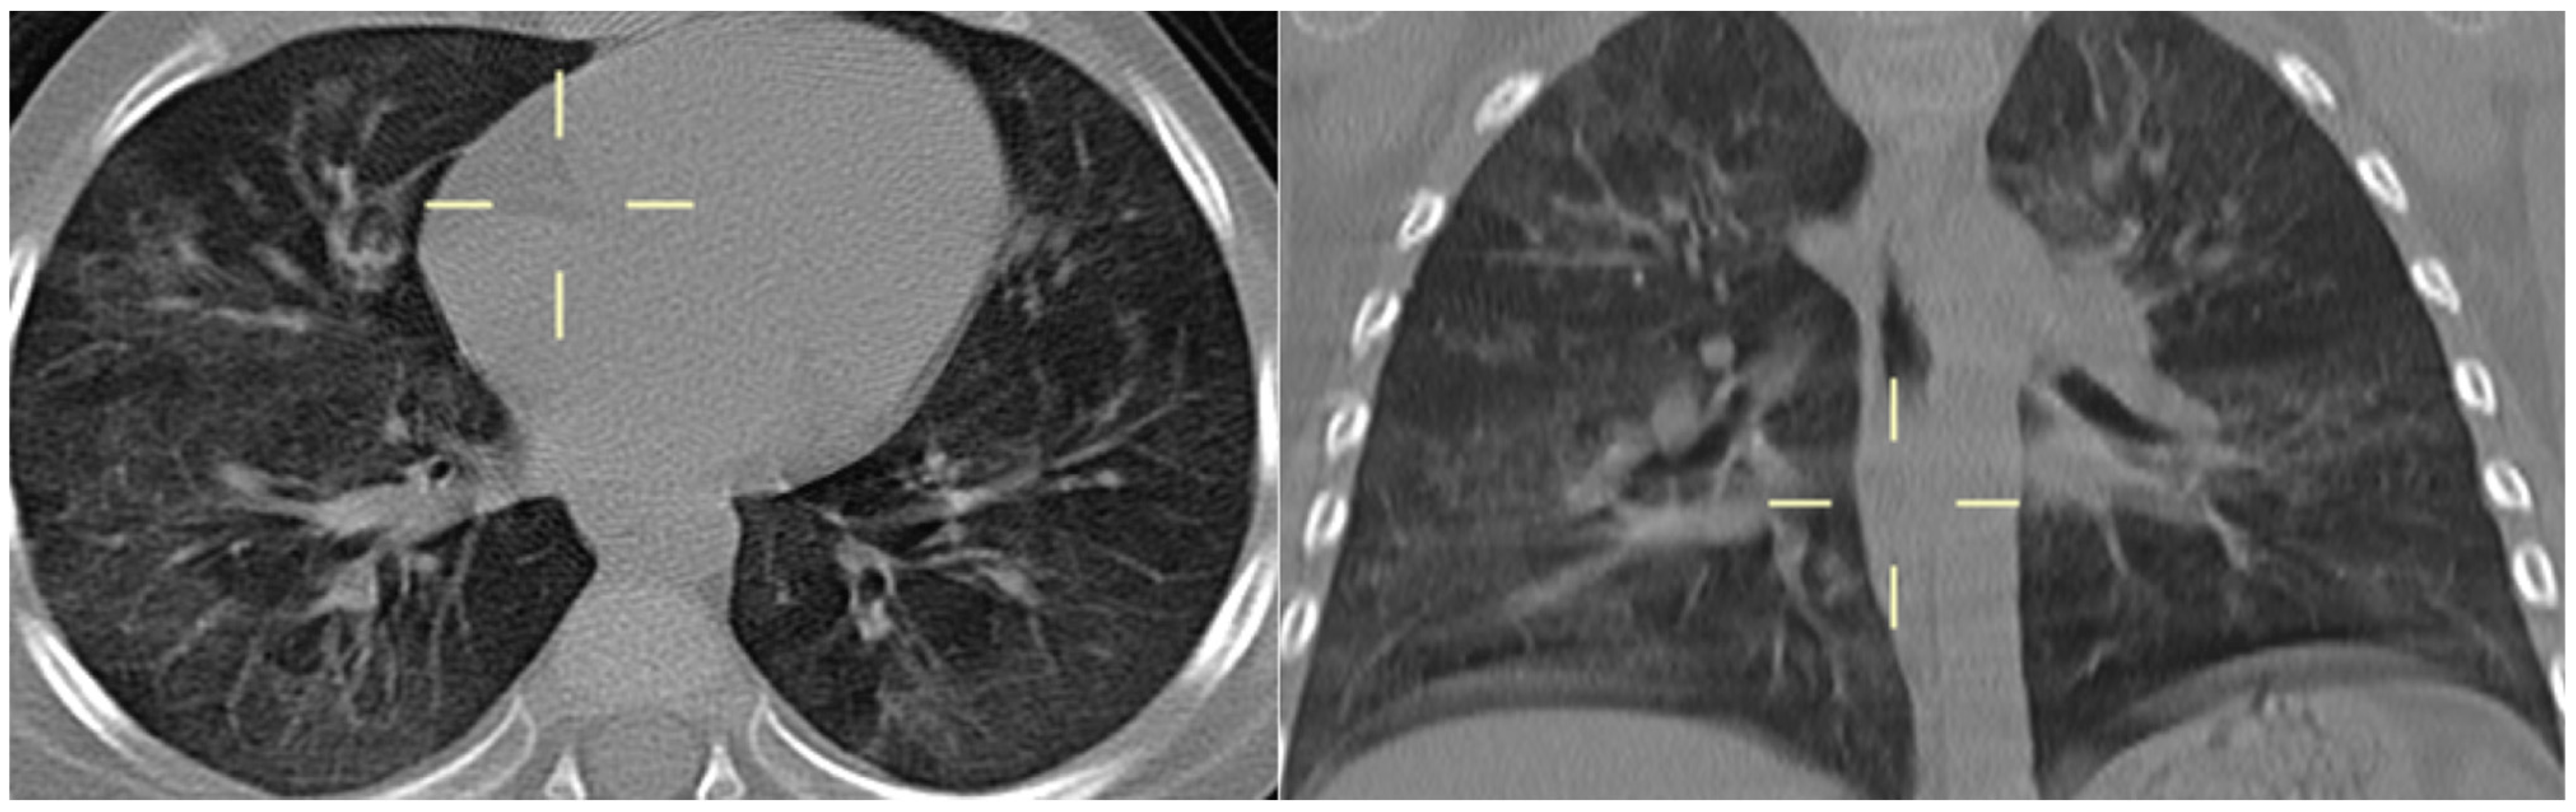

3.5. Radiological Features of PJP in the Study Population